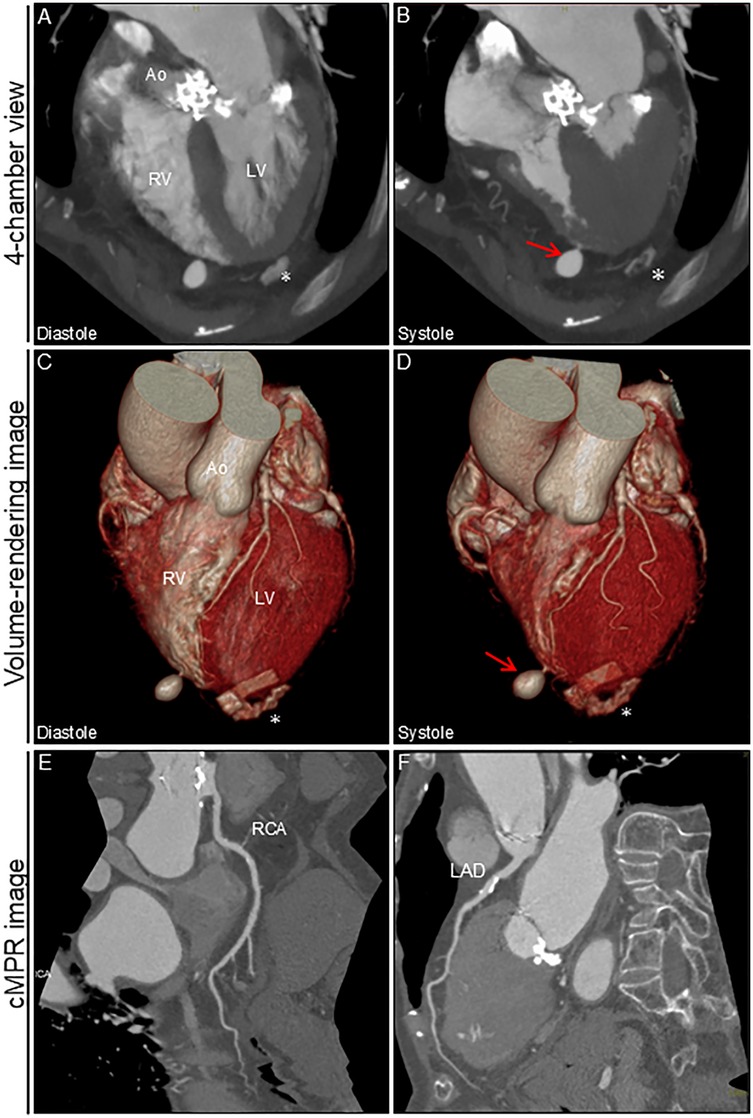

An 88-year-old woman was admitted with symptomatic paroxysmal supraventricular tachycardia that had persisted for three years. The patient had a history of severe aortic stenosis for which transapical transcatheter aortic valve replacement was performed seven years ago. Her initial vital signs were blood pressure of 79/60 mmHg and heart rate of 164 beats/min. The physical examination findings were unremarkable. Laboratory test revealed elevated serum level of brain natriuretic peptide (171.6 pg/ml, reference: <18.4 pg/ml). Electrocardiography revealed narrow QRS tachycardia with a short RP (Supplementary Figure S1A). Tachycardia was terminated with rapid intravenous administration of adenosine triphosphate (Supplementary Figure S1B). However, the patient experienced frequent paraoxymal supraventricular tachycardia episodes. Echocardiography revealed no structural or functional heart abnormalities (Figure 1A; Supplementary Video S1). Unenhanced computed tomography scans showed no biventricular abnormalities suggestive of myocardial infarction or aneurysm. An electrophysiological study was performed four days after admission. Catheters were placed in the high right atrium, the His bundle region, coronary sinus, and right ventricular (RV) apex. Premature ventricular contractions frequently occurred during RFCA, and, hence, the RV pacing catheter was held tightly to avoid the unintended catheter movement. Based on the electrophysiological study, slow/fast atrioventricular nodal reentrant tachycardia was diagnosed. Subsequent successful anatomical slow-pathway ablation was performed according to standard techniques (Figures 1B,C). We excluded any complications, including cardiac tamponade, on postprocedural echocardiography. Follow-up echocardiography revealed RV apical outpouching on postprocedural day 2 (Figures 1D–F; Supplementary Video S2). The patient was asymptomatic, and her vital signs were stable. Physical examination and electrocardiographic findings were unremarkable (Supplementary Figures S1C,D). Follow-up laboratory tests were close to normal. Differential diagnoses of ventricular outpouching include true aneurysms and pseudoaneurysms. Cardiac computed tomography angiography (CCTA) further characterized the morphology and features of the RV apical outpouching (Figures 2A–D). Note the presence of contrast-filled RV outpouching at the apex that protruded during systole, with a maximum diameter of 12.1 mm and a narrow orifice of 1.5 mm with an orifice-to-maximum diameter ratio of 12.4%, suggestive of RVP. CCTA revealed normal coronary arteries (Figures 2E,F). Pericardial effusion was not observed. A detailed review of the computed tomography images confirmed the absence of RVP before the RFCA procedure and its presence after the procedure (Figure 3). Given the temporal relationship between RFCA and the occurrence of RVP without any other identifiable cause, a final diagnosis of iatrogenic RVP was made. After multidisciplinary discussion, taking into consideration that a ventricular pseudoaneurysm is susceptible to cardiac rupture, the patient underwent urgent surgical repair of the RVP. No bleeding was observed in the pericardial sacs. There was no evidence of pericarditis, intrapericardial bleeding, or cardiac rupture except for a slight bulge at the RV apex. Epicardial echocardiography was used to identify the pseudoaneurysm, as such pseudoaneurysm was difficult to identify by visual examination. Subsequent vertical mattress suture repair with Teflon-felt reinforcement was performed for the RVP. The patient's postoperative course was uneventful, and she remained asymptomatic at the one-year follow-up (Supplementary Figure S2).

Figure 2. Cardiac computed tomography angiography image after ablation. 4-chamber view and volume-rendering images during diastole (A,C) and systole (B,D). Outpouching with a narrow neck at the apex of the right ventricle is markedly prominent during systole (arrows). No significant pericardial effusion was observed. cMPR images of RCA (E) and LAD (F) * Denotes the remnants of felt in the left ventricular apex after transapical aortic valve replacement. Ao, aorta; cMPR, curved multi-planar reformation; LAD, left anterior descending artery; LV, left ventricle; RCA, right coronary artery; RV, right ventricle.